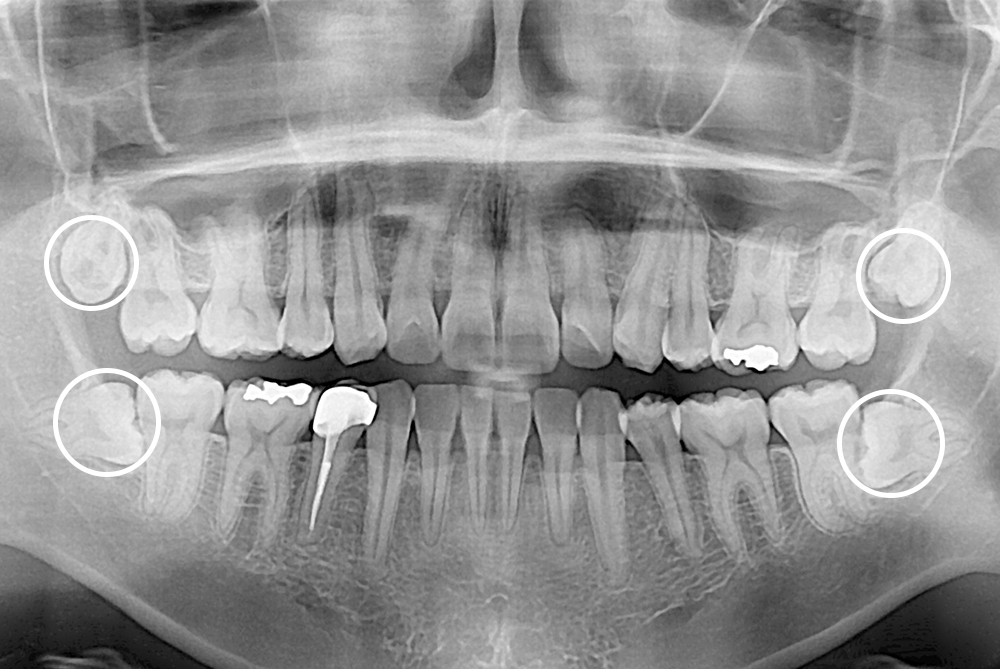

[사랑니] 매복 사랑니 발치

치료전 : 2018-09-04

치료후 : 2018-09-25

세종치과는 구강악안면외과학 박사이신 원장님이 발치하는 치과입니다.